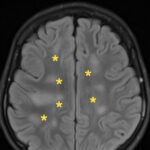

There is a growing body of literature and scientific discovery on pediatric autoimmune encephalitides. This is a heterogenous group of neuroinflammatory conditions leading to often perplexing acute and progressive neurologic and/or neuropsychiatric symptoms. This report demonstrates the evaluation and management of an adolescent with myelin-oligodendrocyte glycoprotein (MOG) antibody-associated fulminant acute disseminated encephalomyelitis (ADEM) in the context of current literature. The featured magnetic resonance imaging uniquely highlights progressive central nervous system lesions detected over the course of the first week of disease.